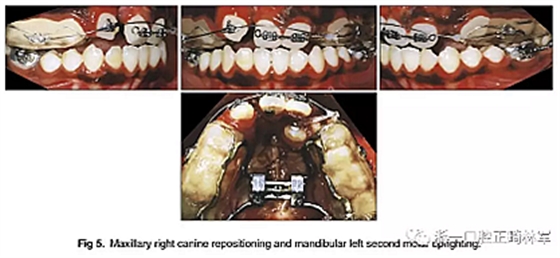

然后,上頜右側(cè)尖牙用0.016英寸的鎳鈦弓絲重新定位,并且使用0.016英寸的不銹鋼片段弓維持中切牙的位置。在下頜弓中,應(yīng)用帶有開放式螺旋彈簧的截面鋼絲直立左側(cè)第二磨牙。它在第一磨牙影響下發(fā)生嚴(yán)重傾斜,受到第三磨牙的壓迫(圖5)。